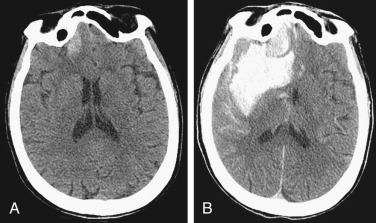

EDH